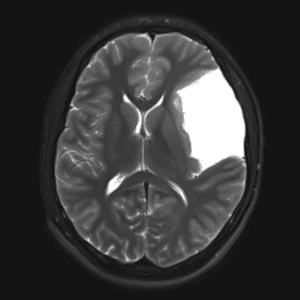

Case #30

Arachnoid cyst